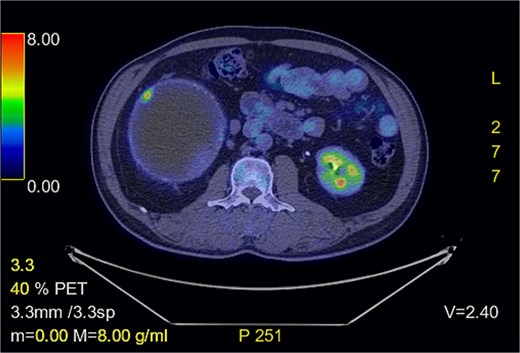

Positron-emission tomography (PET) scan with F18-Fluorodeoxy-glucose (FDG) and C11-Acetate, and combined contrast-enhanced computerized tomography (CT) revealed a predominantly cystic mass measuring ~14.8 × 17.9 × 18.6 cm located on the right side of the abdomen, arising from the retroperitoneal space with close approximation to the adrenal gland. It displaced the adjacent organs, including pancreas and the right kidney; A tiny mural calcification and focal hypermetabolic activity within the cyst wall raised the possibility of malignant transformation (Figs 1–4).

Cystic mass with mural calcification and tissue components in the posteroinferior portion, closely abutting the right kidney and adrenal.